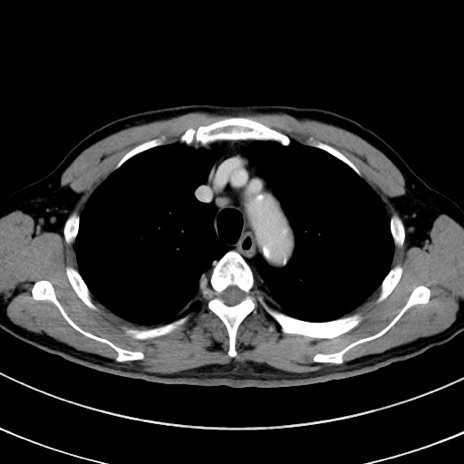

冠状断像